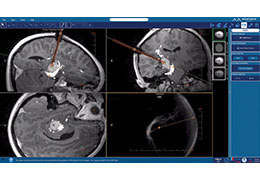

Coregistration of MRI with EEG & MEG

Coregistration of MRI with EEG & MEG

For an easy superposition of the results of source analysis with individual EEG and MEG data, BrainVoyager provides an interactive link to BESA (Brain Electrical Source Analysis). The bidirectional connection of the two programs allows for source seeding from fMRI clusters with one mouse click.